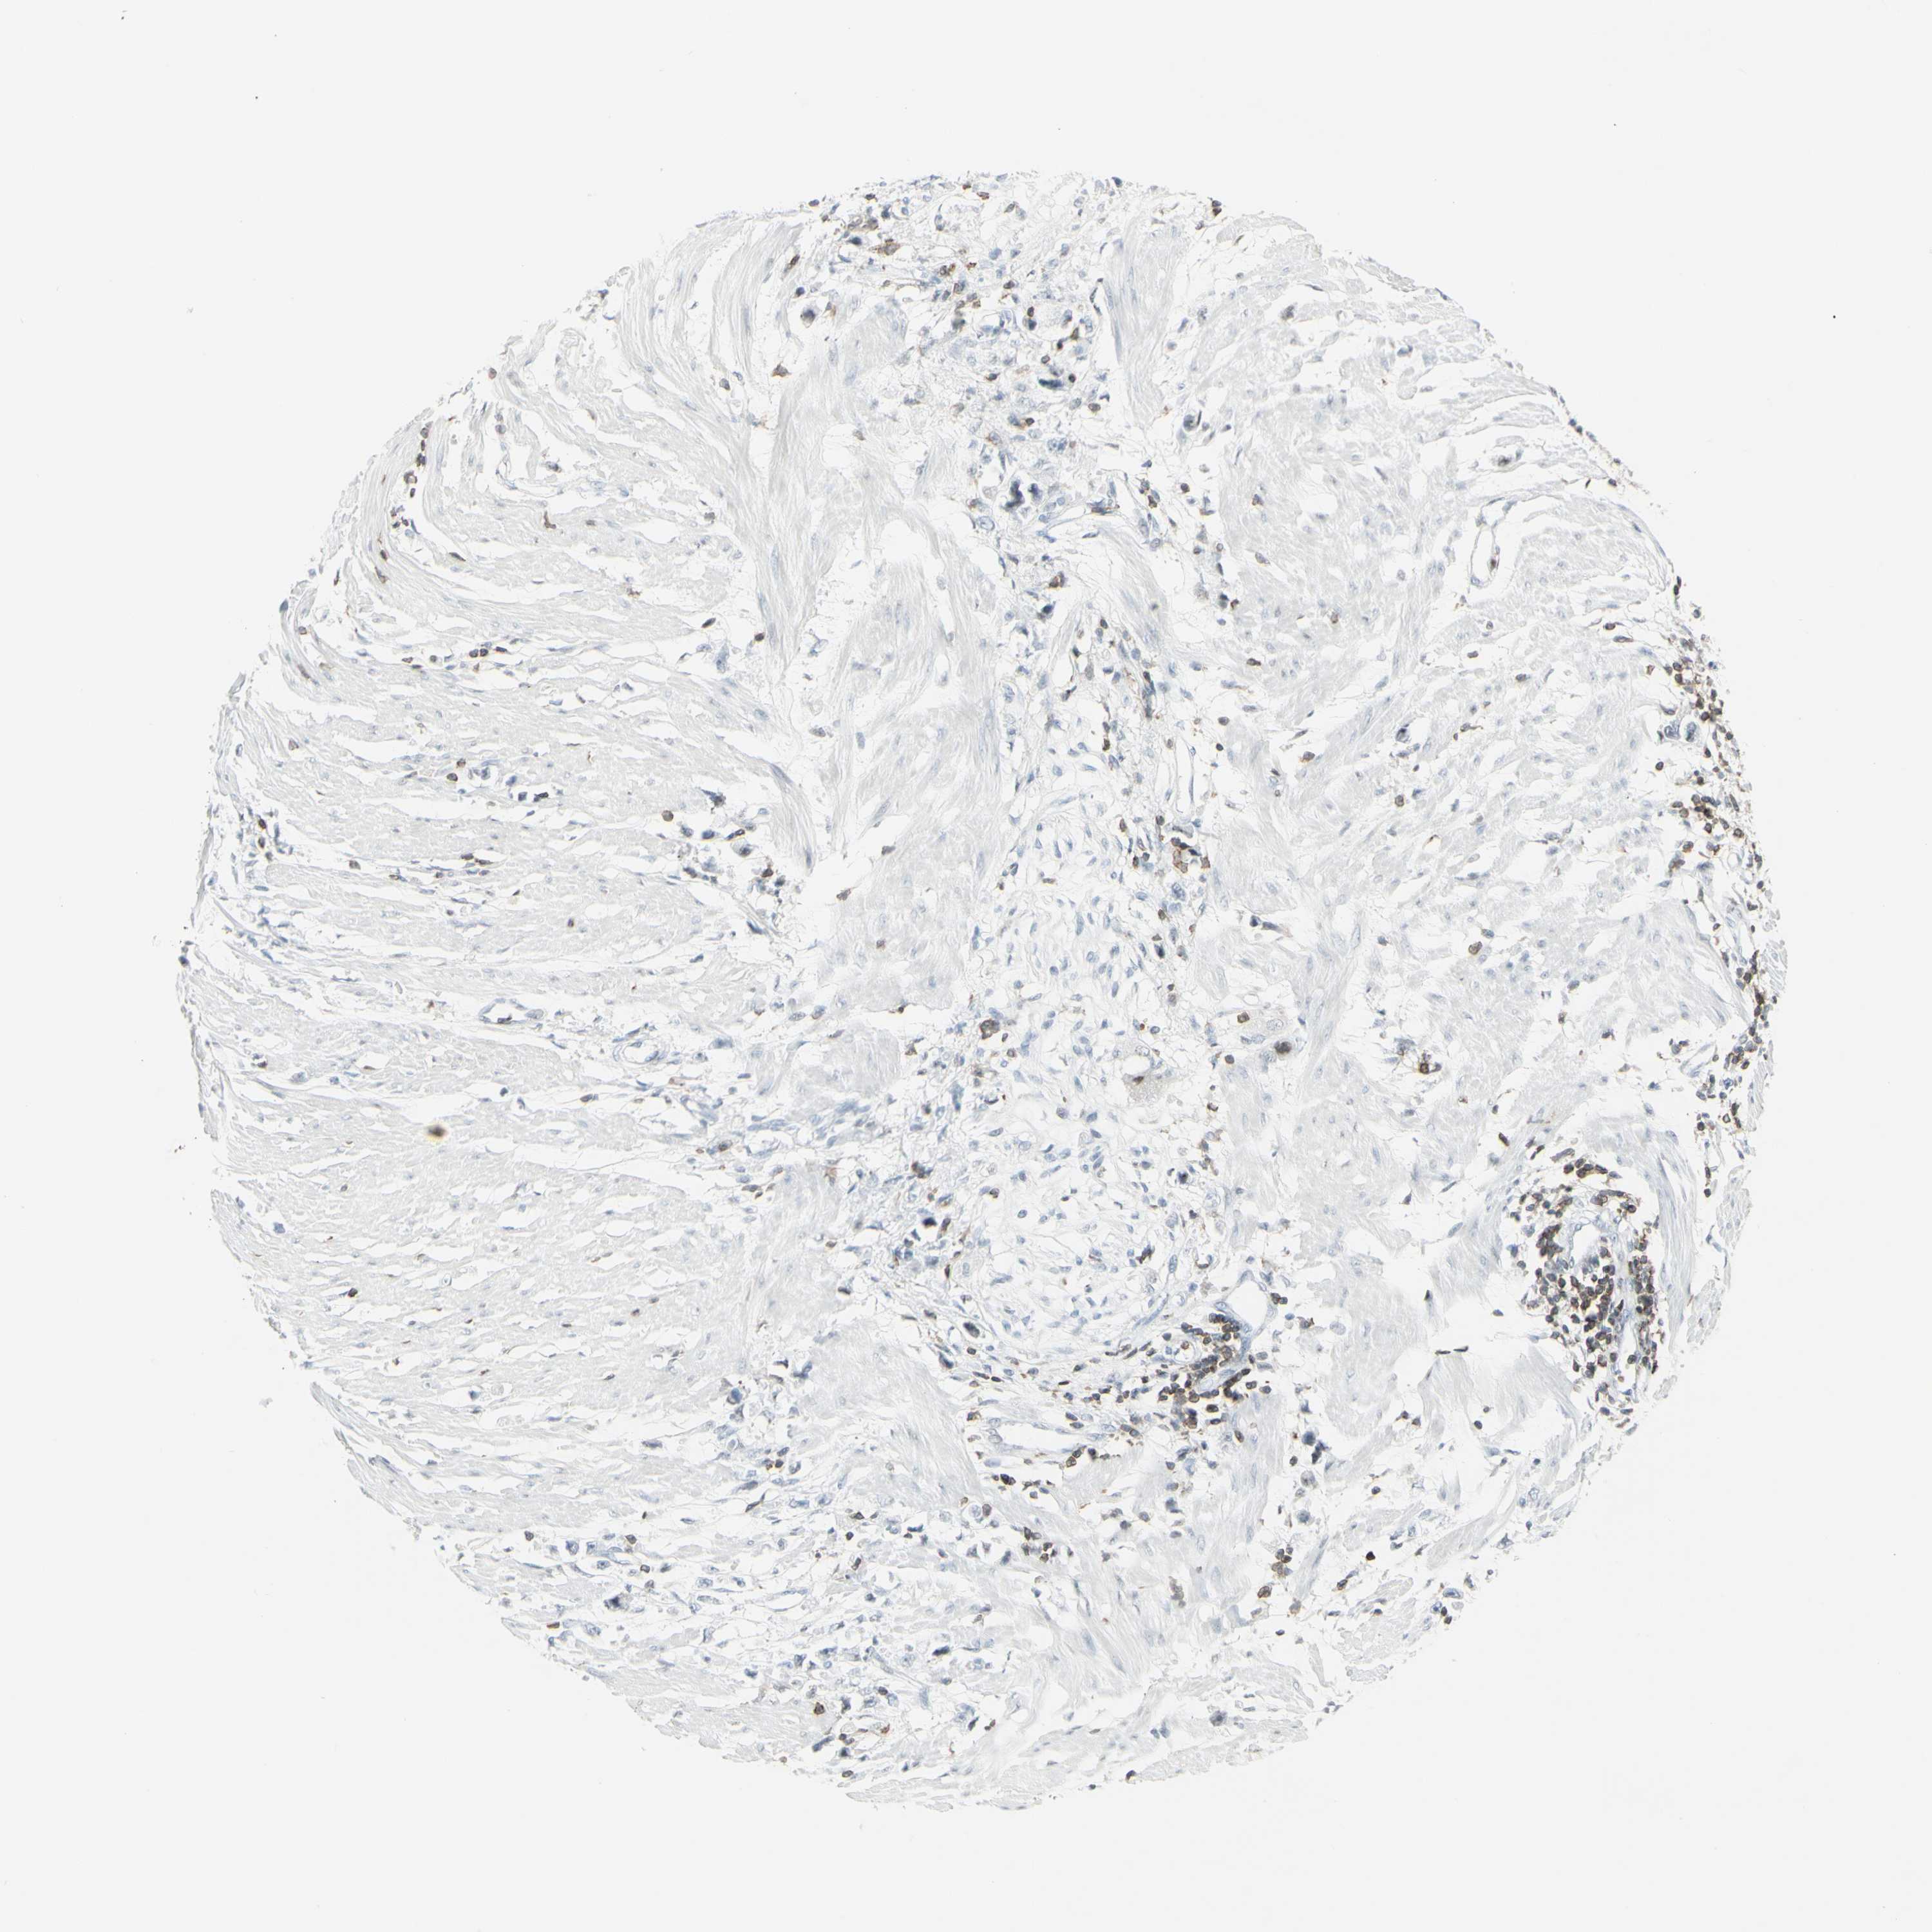

STOMACH CANCER - Protein expressioni

A mouse-over function shows sample information and annotation data. Click on an image to view it in a full screen mode. Samples can be filtered based on level of antibody staining by selecting one or several of the following categories: high, medium, low and not detected. The assay and annotation is described here.

Note that samples used for immunohistochemistry by the Human Protein Atlas do not correspond to samples in the TCGA dataset.

Antibody stainingi

Antibody staining in the annotated cell types in the current human tissue is reported as not detected, low, medium, or high, based on conventional immunohistochemistry profiling in selected tissues. This score is based on the combination of the staining intensity and fraction of stained cells.

Each image is clickable and will lead to virtual microscopy that enables deeper exploration of all samples and also displays staining intensity scores, fraction scores and subcellular localization as well as patient and tissue information for each sample.

Antibody HPA010964

Staining

High

Medium

Low

Not detected

Intensity

Strong

Moderate

Weak

Negative

Quantity

>75%

75%-25%

<25%

None

Location

Nuclear

Cytoplasmic/membranous

Cytoplasmic/membranous,nuclear

Adenocarcinoma, NOS